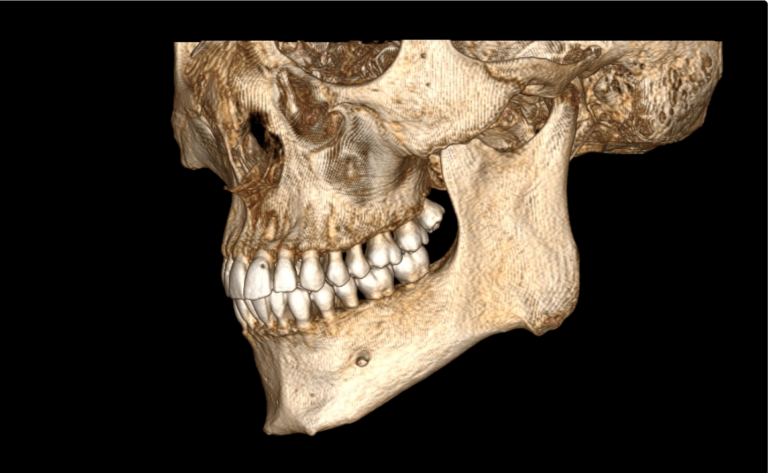

Мультиспиральный томограф выполняет послойное сканирование области верхней и нижней челюстей с помощью рентгеновских лучей, а затем, используя компьютерную обработку данных, создает 3D-модели исследуемой зоны. Современные модели томографов проводят круговое сканирование по спирали, делая срезовые снимки на расстоянии 0,5 мм друг от друга. Затем на основе этих данных реконструируются детальные изображения челюстно-лицевой области в трехмерном формате.

- Информативность. Дентальная КТ позволяет обнаружить признаки патологии, которые не видны на обычных (2D) панорамных снимках – ортопантомограммах. На двухмерных рентгенограммах различные структуры накладываются друг на друга. В отличие от этого пространственные модели дают возможность рассмотреть челюстно-лицевой аппарат в различной проекции и плоскости.

- Широкие возможности диагностики. На трехмерных изображениях можно увидеть в целом верхнюю и нижнюю челюсть, включая гайморовы пазухи, височно-нижнечелюстные суставы. Помимо костной ткани при проведении КТ можно оценить состояние окружающих мягких тканей. Это бывает особенно важно при выборе оптимального способа протезирования и имплантации, при подозрении на опухолевые процессы, при планировании оперативного вмешательства.